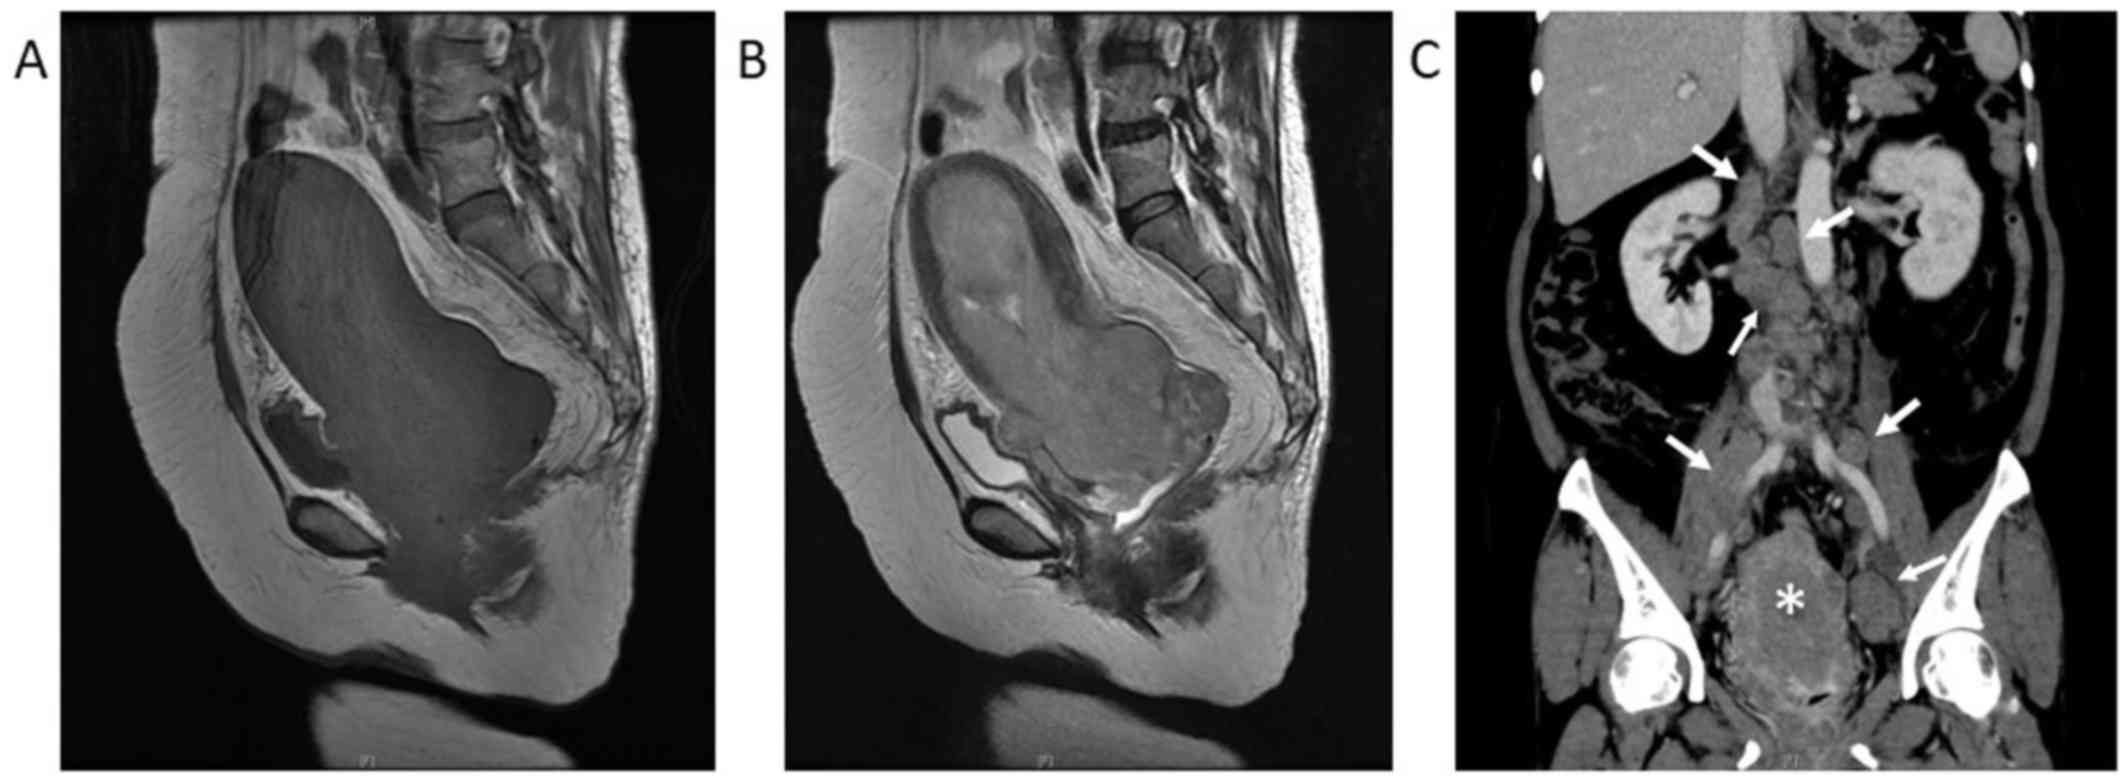

A 52-year-old woman (gravida 6, para 4), with no history of gynecological disorders, was referred to Toyooka Hospital (Toyooka, Japan) due to genital bleeding in February 2016. The patient had been taking a low-dose contraceptive pill for 18 months prior to the consultation to control functional bleeding. Regular gynecological physical examinations 3 months prior to the consultation failed to identify any abnormalities. The patient consulted her primary care doctor due to continuous genital bleeding for 50 days. The doctor diagnosed the patient with anemia [hemoglobin (Hb) level, 8.8 g/dl] and detected a uterine cervical polyp; the patient was subsequently referred to Toyooka Hospital. Upon pelvic examination at the Department of Gynecology, a cauliflower-shaped tumor, ~80 mm in diameter, was identified in the vaginal cavity. Continuous bleeding from the tumor surface was observed. Anemia was also observed on blood examination. The tumor appeared to develop from the uterine os, suggesting that it originated in the uterine cavity and extended into the vaginal cavity. Examination using ultrasound revealed a tumor occupying the entire uterine cavity and was attached to the fundus through a stalk. Magnetic resonance imaging examination revealed a homogeneous tumor, sized 16.9×8.4×7.8 mm, in the endometrial cavity, protruding into the vaginal cavity. A coronal contrast-enhanced computed tomography scan revealed a heterogeneously enhanced uterine tumor and enlargement of the paraaortic lymph nodes, external iliac lymph nodes, and partially necrotic internal iliac lymph nodes, suggesting lymph node metastasis. There was no detectable invasion of the tumor into the bladder or rectum on diagnostic imaging (Fig. 1). Laboratory data on admission included Hb 8.7 g/dl, C-reactive protein 8.73 mg/dl, creatinine 0.77 mg/dl, lactate dehydrogenase 814 U and carbohydrate antigen-125 36.5 U/ml. Histological examination of a biopsy sample from the tumor revealed atypical cells and necrotic tissue. The tumor cells were medium-large in size, with abundant cytoplasm and prominent nucleoli (Figs. 2A and B). Immunohistochemically, the tumor cells were positive for CD56 and synaptophysin (Figs. 2C and D), and negative for cytokeratin AE1/AE3, chromogranin A, P40, α-smooth muscle actin (SMA), S100, CD10 and CD34. The Ki-67 index was ~85% (Fig. 2E). Based on the histological characteristics and results of the immunochemical staining, the tumor was diagnosed as LCNEC. The blood levels of neuron-specific enolase (NSE) and proGRP was measured, and revealed that the level of proGRP was normal, but the level of NSE was extremely high (240.4 ng/ml; normal range, ≤10 ng/ml). Due to the poor condition of the patient and extent of tumor spread, palliative care using morphine hydrochloride (600 µg/kg/day) was administered in an attempt to alleviate the symptoms. However, the tumor rapidly progressed and the patient succumbed to the disease 36 days after admission.

Figure 1.

Diagnostic imaging of the tumor. (A) Sagittal T1-weighted magnetic resonance imaging (MRI) without fat saturation and (B) T2-weighted MRI of the abdomen and pelvis revealed a sizeable homogeneous tumor in the endometrial cavity, which protruded into the vaginal cavity. (C) Coronal contrast-enhanced computed tomography scan revealed a heterogeneously enhanced uterine tumor (*) with enlargement of multiple para aortic and external iliac lymph nodes, and partially necrotic internal iliac lymph nodes (arrows).